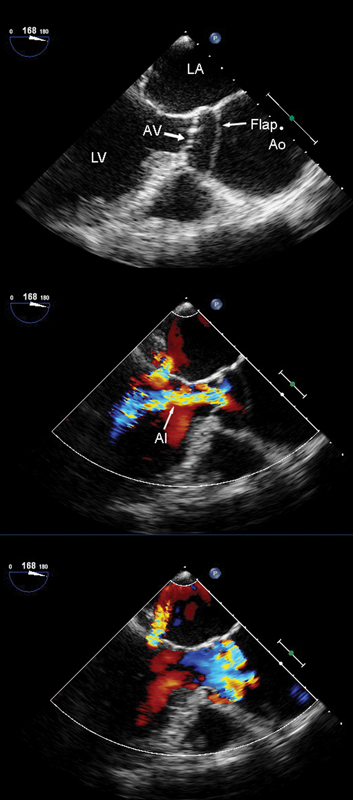

فحوصات تشخيصية لبعض امراض القلب والشرايين التاجية